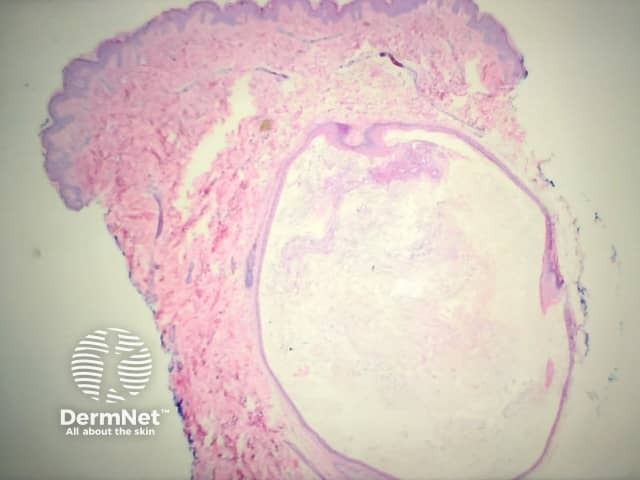

A skin biopsy may confirm the diagnosis. Histopathology shows stratified-squamous epithelium with a granular layer that surrounds a cystic space filled with laminated keratin and a variable number of vellus hair shafts.

Low power view of cyst

Hair shafts within cyst

High power view